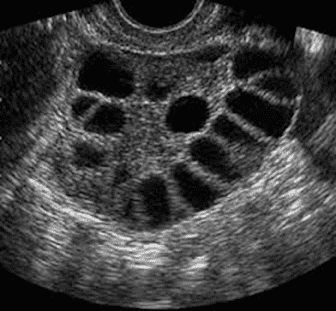

The doctor may also order certain tests and exams, one of which would be a pelvic ultrasound. In PCOS, the ovaries could appear enlarged with multiple (more than 12) cysts/follicles on each side. Below is an example of what a PCOS ovary would look like on ultrasound.